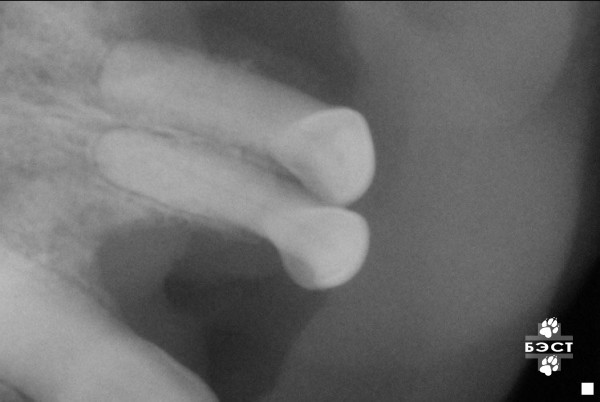

Рентгенологическая диагностика саркомы у кошек

Раздел: Визуальный дайджест